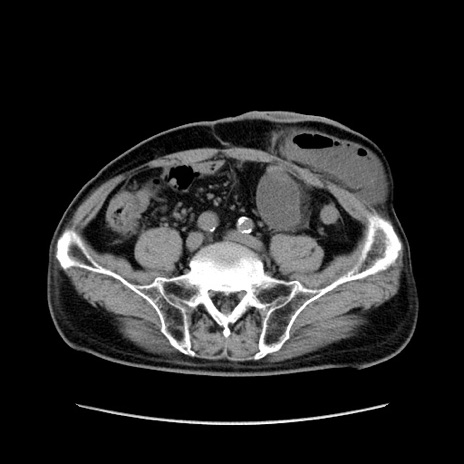

症例24(横断像)

【症例】80歳代男性

【主訴】左側腹部痛、嘔吐

【現病歴】本日早朝より左腹部に痛みあり。昼頃嘔吐認めたため、救急要請。

【既往歴】直腸癌(Mile手術)、胆摘

【身体所見】意識清明、BT 35.9℃、BP 221/93mmHg、SpO2 97%(RA) 、腹部:左ストーマ周囲に限局性の腹部膨隆あり。 膨隆部自発痛・圧痛あり・軟。

【データ】WBC 7700、CRP 0.09